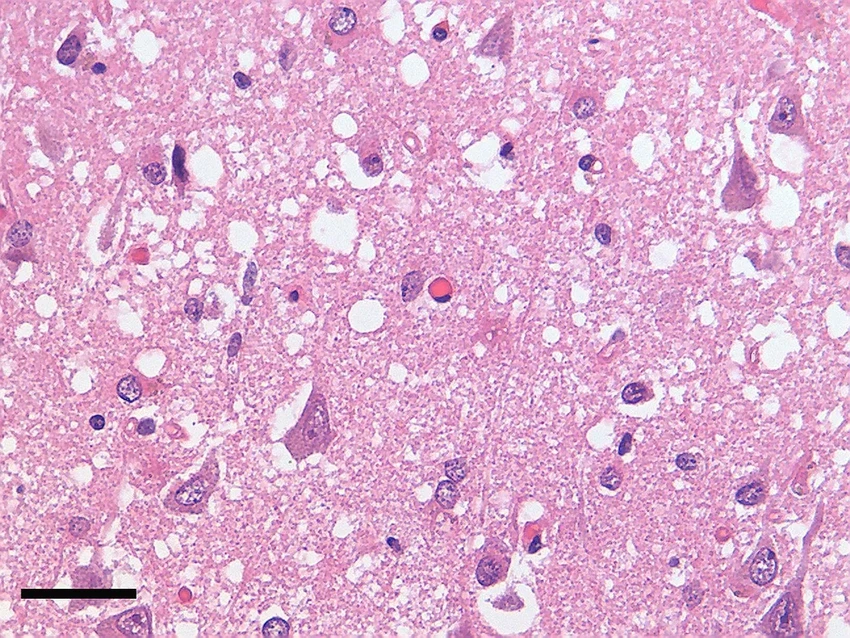

Многие нейродегенеративные болезни — Альцгеймера, Паркинсона — это, по сути, трагедия на молекулярном уровне. Гены сбиваются с ритма и начинают штамповать белки с фатальными ошибками. Эти белки-уродцы засоряют и убивают нейроны. Но что, если просто остановить этот бракованный конвейер, не трогая сам чертёж — ДНК? Природа знает этот трюк и использует его постоянно — через процесс метилирования. Исследователи просто направили этот природный механизм точно в цель: заставили гены, производящие смертельные прионы, замолчать. Просто и гениально.

Прионные болезни — это кошмар наяву. Они возникают, когда безобидный белок PrP вдруг принимает неправильную форму, слипается в комки и методично разрушает нервные клетки. Представьте себе редкое заболевание — фатальную семейную бессонницу, которое лишает человека сна и неумолимо ведёт к гибели. Всё это — дело «рук» прионов.

Когда CHARM доставили в мозг мышей, результат превзошёл ожидания: производство рокового белка PrP упало более чем на 80% по всему мозгу. Это намного выше минимального порога, необходимого для терапевтического эффекта! А после выполнения миссии CHARM, словно агент-невидимка, самоуничтожается, не оставляя следов в клетке. Идеальный инструмент.